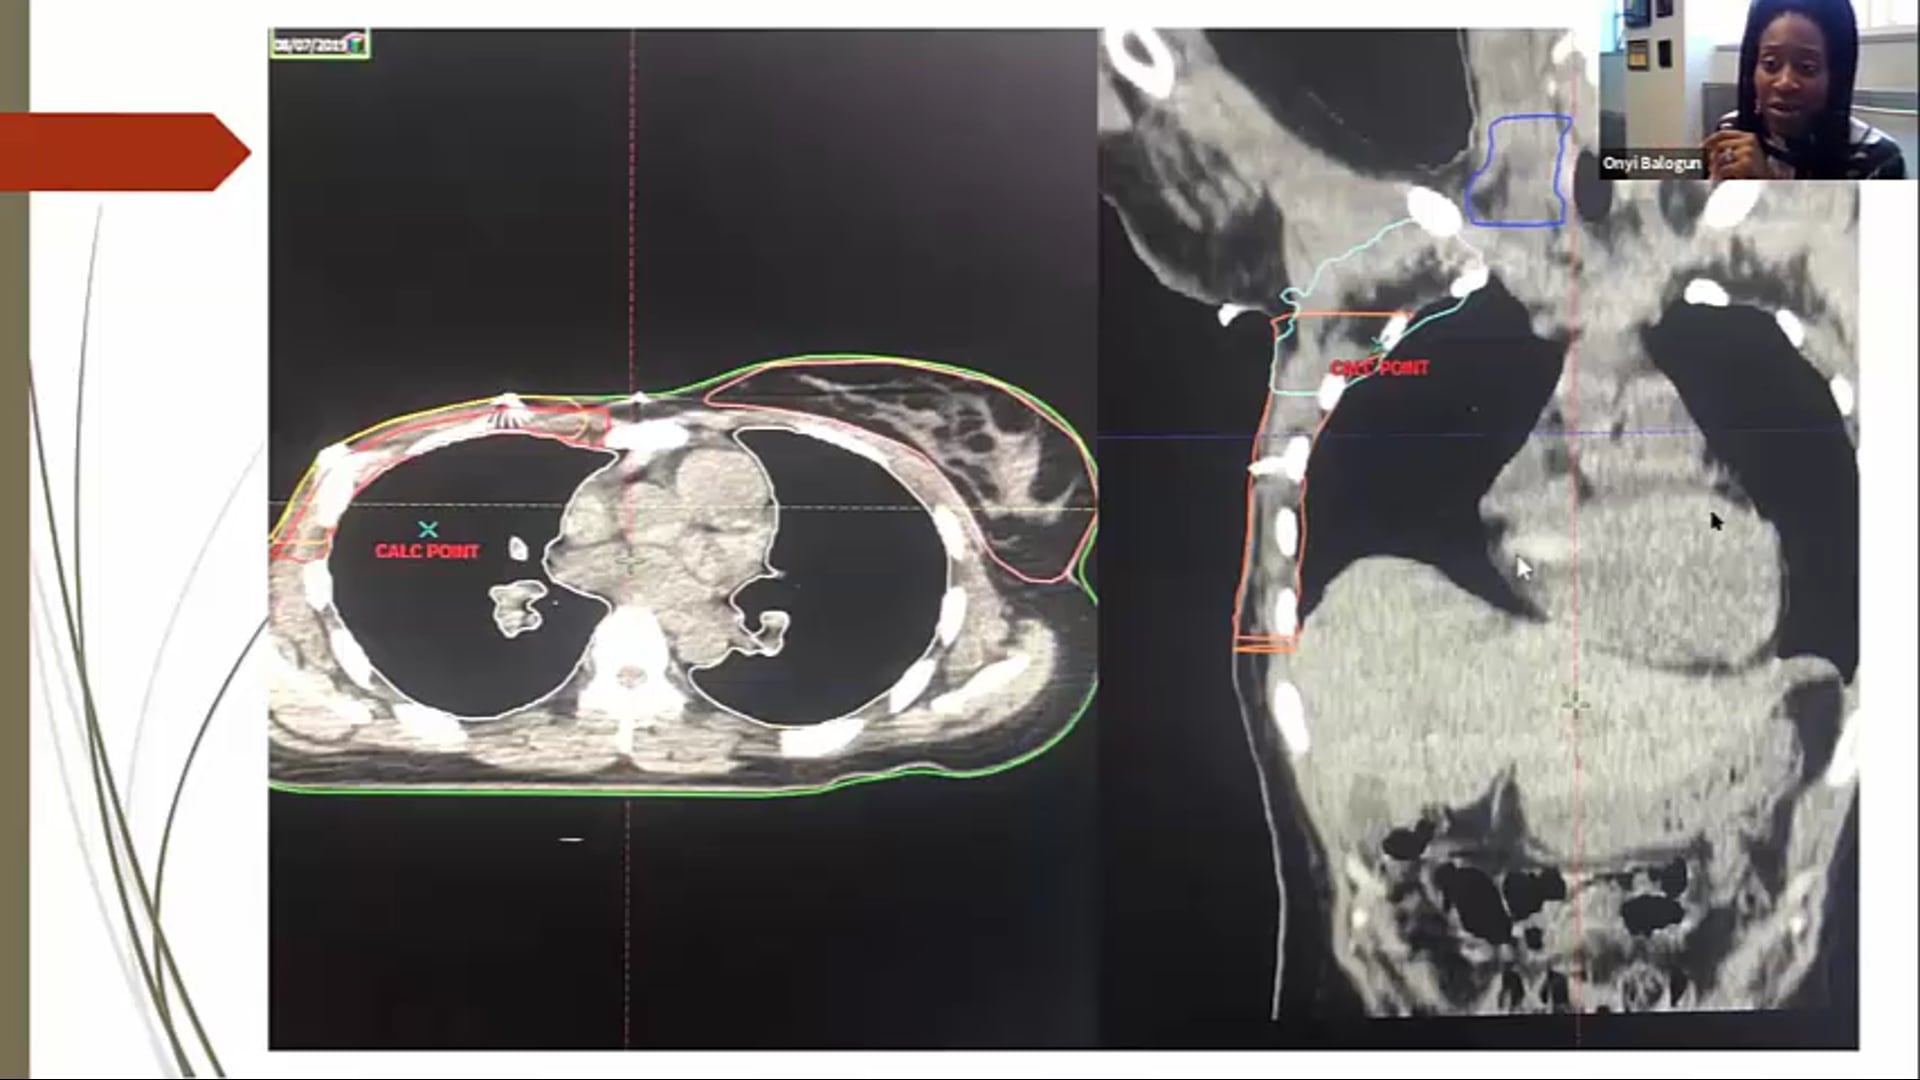

08/05/19 - Dr. Onyinye Balogun - Radiation Oncology - Breast Africa

Invasive Ductal Ca, Neo-adjuvant chemo, auxiliary node treatment, chest wall bolus, dose, treatment fields, contouring,